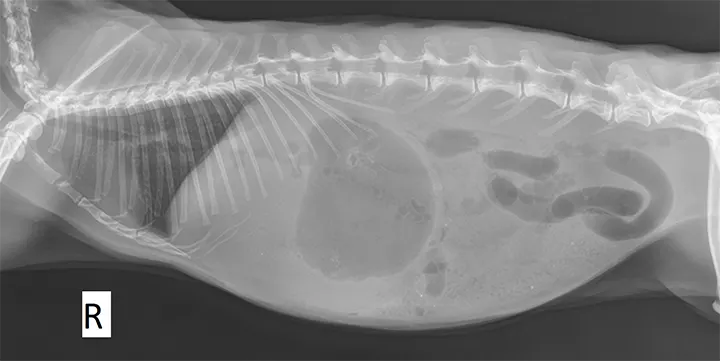

Right lateral radiograph of a 1-year-old, intact male Holland lop rabbit presented with a history of reduced activity, anorexia, and no fecal output since the previous day. Blood glucose was 328 mg/dL (reference range, 110-160 mg/dL). The stomach appears distended and fluid-filled with a gas cap, and an abnormal gas pattern can be seen in the small intestines. The combination of history, clinical signs, physical examination, hyperglycemia, and radiographic findings is highly suggestive of intestinal obstruction.